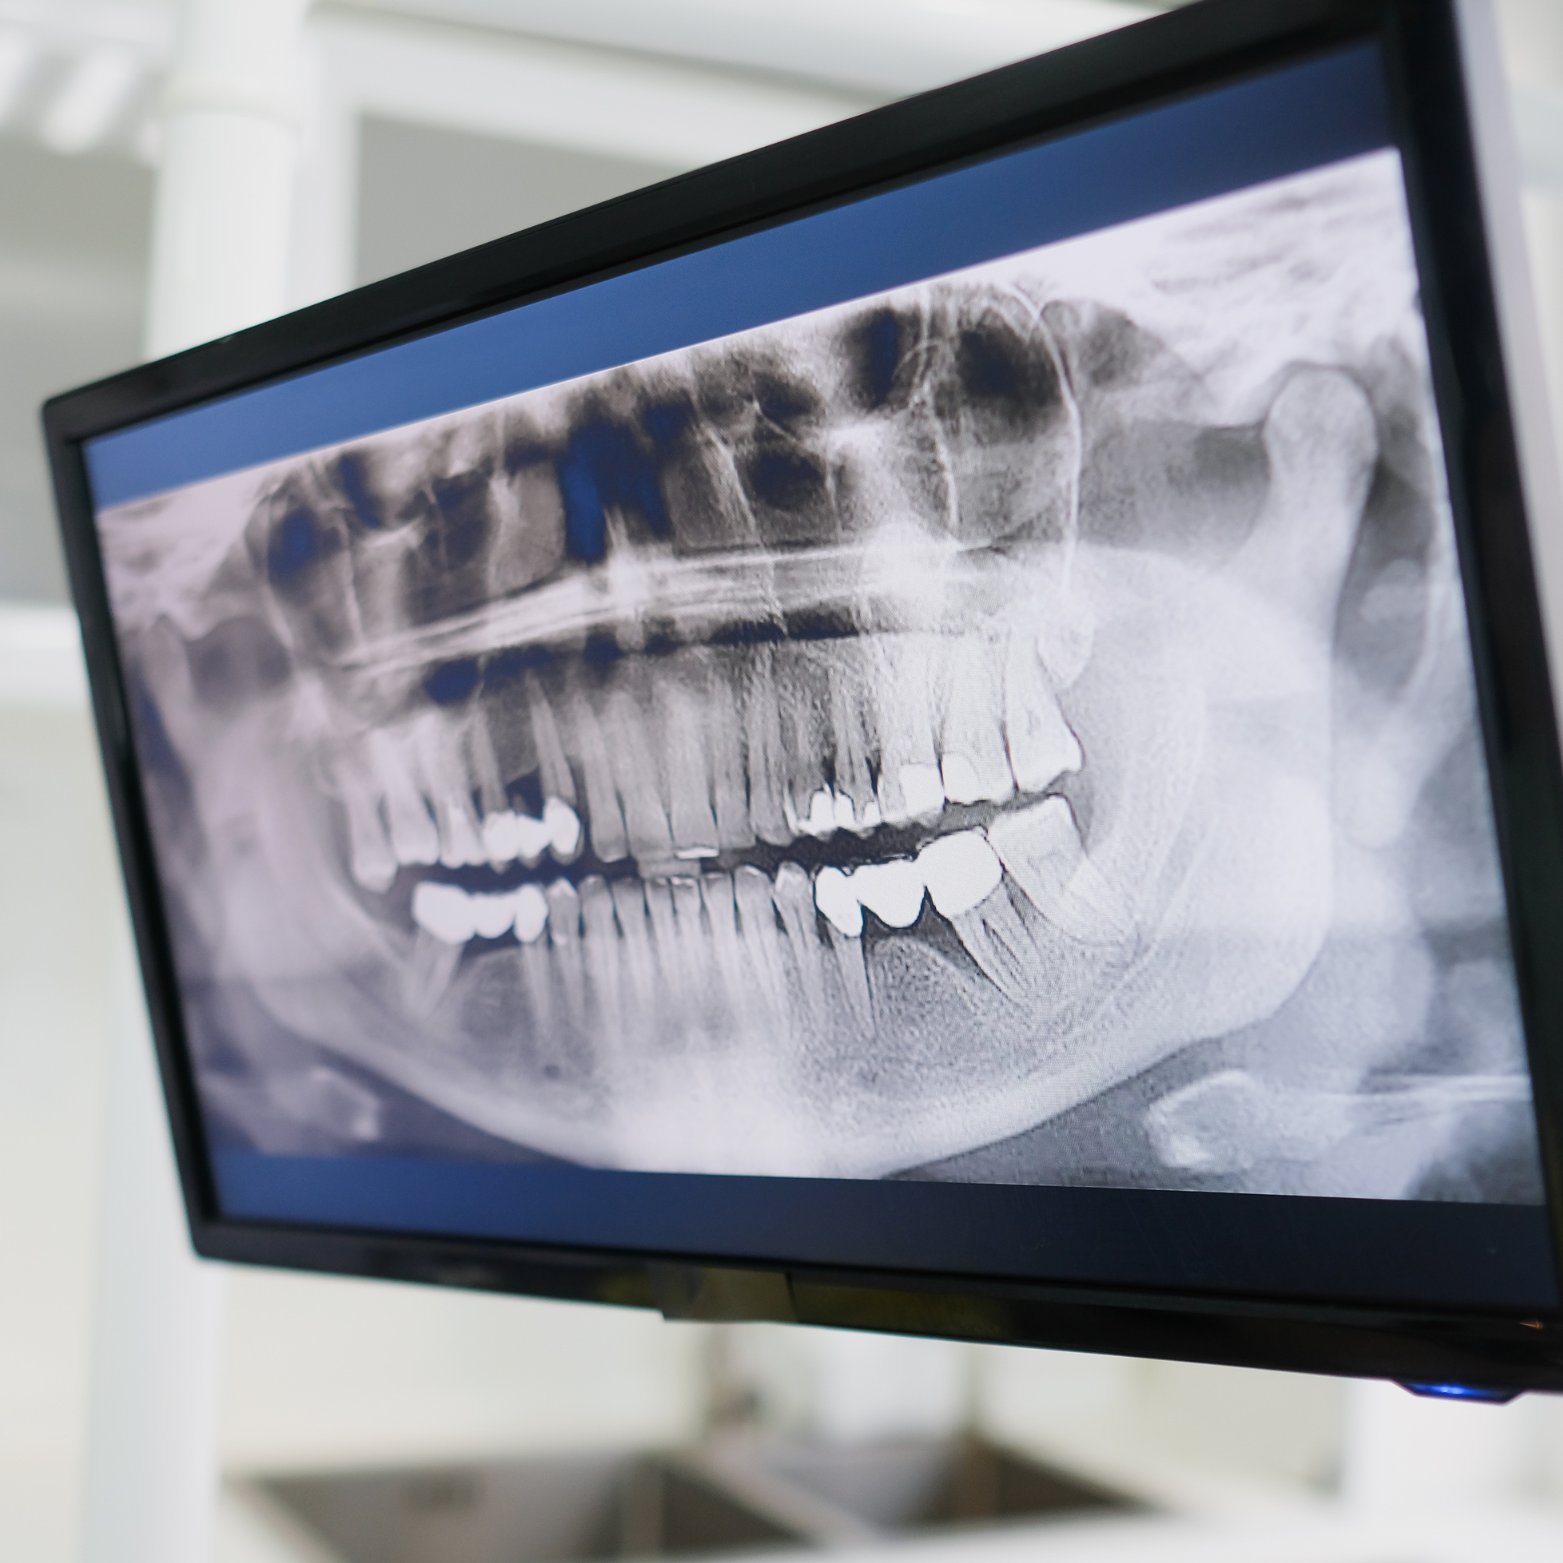

EXTRAORAL X-RAY

We offer panoramic and cephalometric imaging to efficiently screen for bone and tooth lesions, delivering comprehensive views of the entire jaw, teeth, and surrounding structures in a single, low‑radiation scan. This advanced diagnostic tool helps our dentists detect abnormalities early, plan treatments more accurately, and monitor changes over time to ensure optimal oral health and predictable treatment outcomes.

Our extraoral X‑ray technology delivers exceptional image quality: combines advanced sensors and precise beam collimation to produce sharp, high‑resolution images that reveal fine anatomical detail for accurate diagnosis and treatment planning, while strict protocols and built‑in safety features keep radiation exposure to an absolute minimum so you can feel secure about radiation hazards.